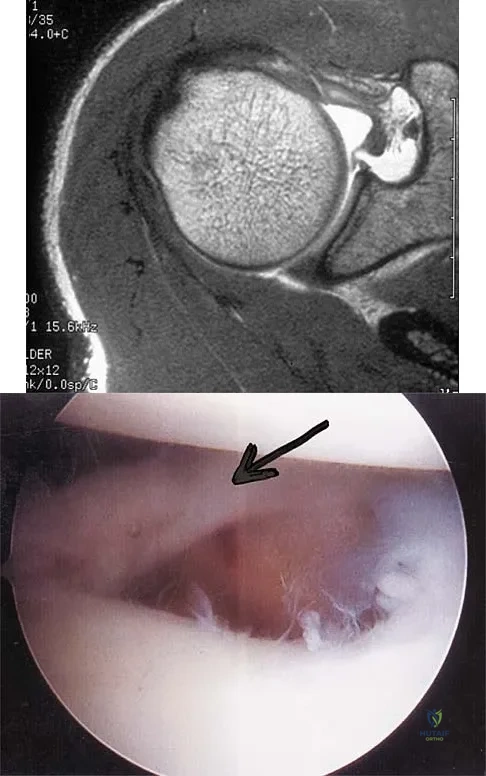

Question 61

A patient has right shoulder pain. Figure 1a shows a gadolinium-enhanced transverse MRI scan at the level of the coracoid. Figure 1b shows an arthroscopic view of the anterior structures from a posterior portal. These images reveal which of the following findings?

Explanation